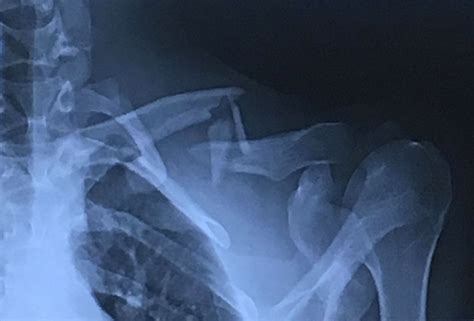

To confirm a clavicle fracture, a healthcare provider will perform a physical examination and order imaging tests. Common diagnostic tools include:

• X-rays: These provide clear images of the bone and can show the location and severity of the fracture.

• CT Scans: In some cases, a CT scan may be ordered to get a more detailed view of the fracture, especially if surgery is being considered.